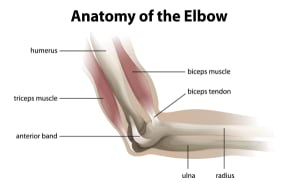

Elbow Preservation

The elbow is a complex joint that bridges the upper arm and forearm, featuring two critical joints: the humeroulnar joint (allowing arm bending) and the radiocapitellar joint (permitting forearm rotation). The joint's stability is ensured by a robust network of ligaments, muscles, and tendons.Elbow injuries frequently result from overuse, leading to symptoms such as pain, joint instability, restricted range of motion, and occasionally joint locking. Proper care and treatment are crucial for maintaining elbow health and function.